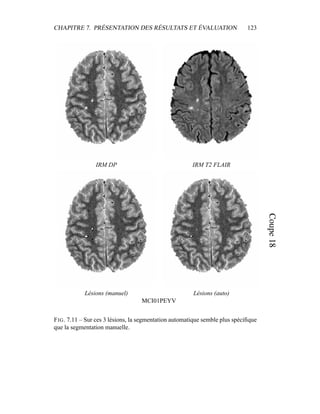

images de la base de travail. Le masque est précis, même sur les coupes du cer-

velet. Il peut présenter certaines irrégularités, auxquelles il faudra faire attention

dans le modèle de segmentation en tissus. Un tel masque nous permet cependant